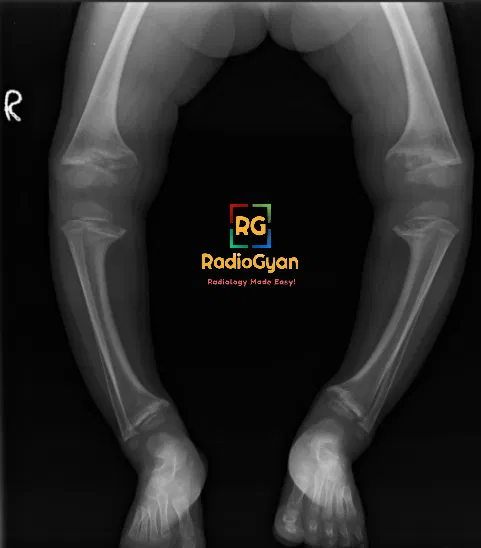

Rickets typically presents with metaphyseal cupping, splaying, and fraying at the growth plates, especially in long bones like the distal femur and proximal tibia. Loss of the thin, dense zone of provisional calcium at the physis-metaphysis interface is a hallmark feature.

- Metaphyseal Cupping: Refers to the flaring out or widening of the metaphysis, which is the wide portion at the end of a long bone where growth occurs.

- Splaying: This term describes the widening of the metaphyseal region, giving a characteristic appearance on imaging studies.

- Fraying: Seen as irregularity or roughening of the edges of the metaphysis, indicating abnormal bone formation.

- Loss of Zone of Provisional Calcium (ZPC): Typically, there is a thin, dense, well-defined zone at the interface of the growth plate and metaphysis that appears disrupted in rickets.

- Lengthening of Radiolucent Physis: The growth plate appears longer than usual due to increased unossified cartilage in affected bones.

- Most Pronounced in Long Bones: Rickets affects areas of rapid bone growth, such as the distal femur, proximal tibia, and distal radius, where these imaging features are more prominent.

Common clinical features of rickets include short stature, genu varum (bow-legged appearance), metaphyseal swelling, pain, and fractures. Other manifestations can include craniotabes (soft bones easily indented), frontal bossing, delayed closure of anterior fontanelle, scoliosis, and rachitic rosary (palpable expanded anterior ribs).